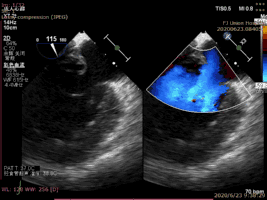

病例1术前二尖瓣反流为重度